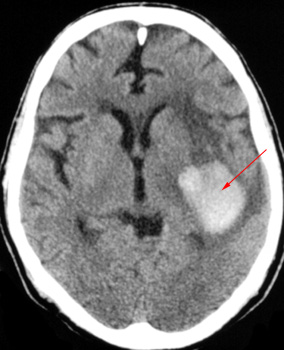

Head CT > Stroke > Hypertensive Hemorrhage

Hypertensive hemorrhage accounts for approximately 70-90% of non-traumatic primary intracerebral hemorrhages. It is commonly due to vasculopathy involving deep penetrating arteries of the brain. Hypertensive hemorrhage has a predilection for deep structures including the thalamus, pons, cerebellum, and basal ganglia, particularly the putamen and external capsule. Thus, it often appears as a high-density hemorrhage in the region of the basal ganglia. Blood may extend into the ventricular system. Intraventricular extension of the hematoma is associated with a poor prognosis.